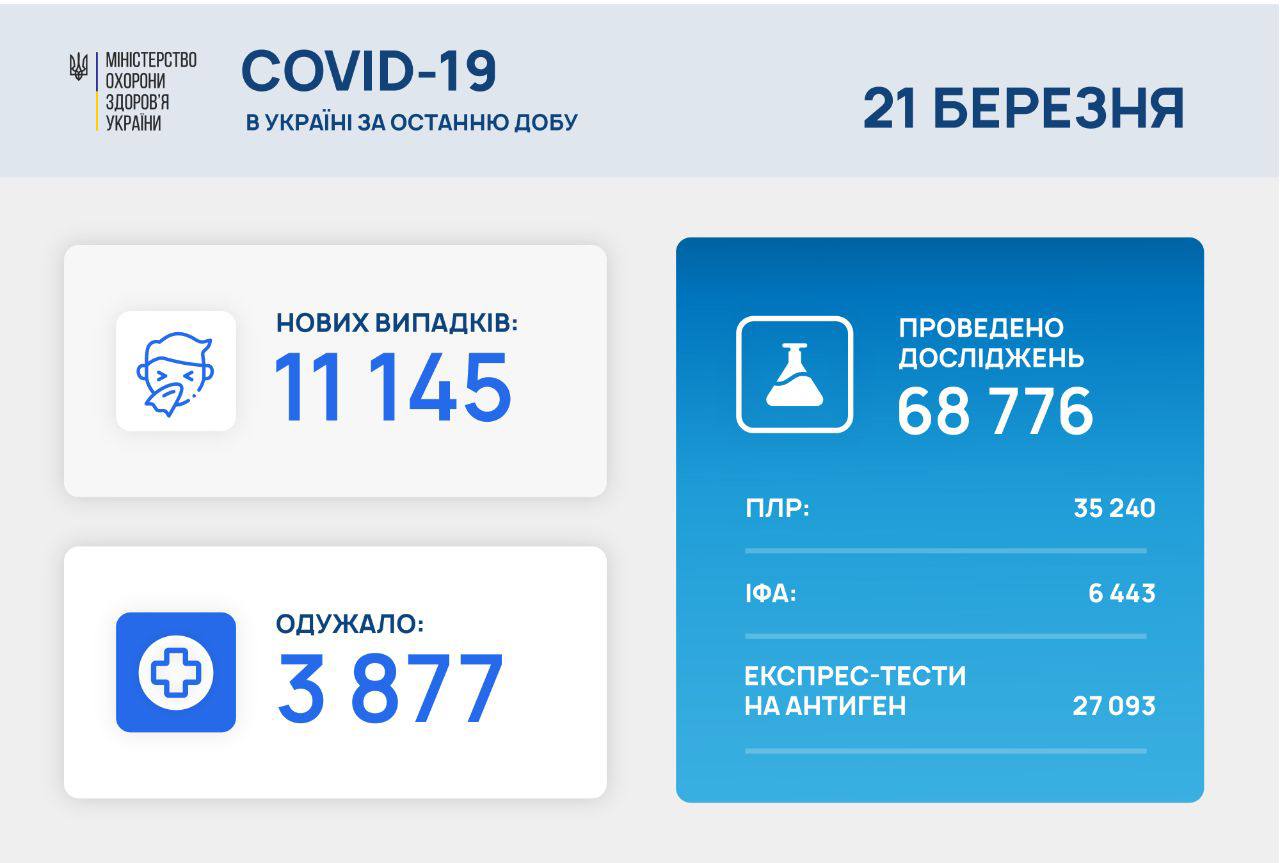

МОЗ: Уперше з початку пандемії було зроблено понад 100 тисяч ПЛР-досліджень за добу